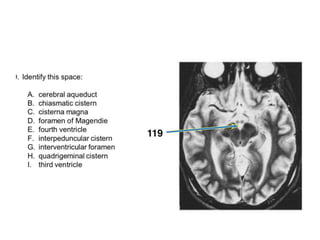

A. cerebral aqueduct

B. fourth ventricle

C. inferior cerebellar peduncle

D. interpeduncular fossa

E. middle cerebellar peduncle

F. oculomotor nerve

G. optic nerve

H. optic tract

I. prepontine cistern

J. third ventricle

K. trigeminal nerve

L. trochlear nerve

M. vagus nerve

N. vestibulocochlear nerve